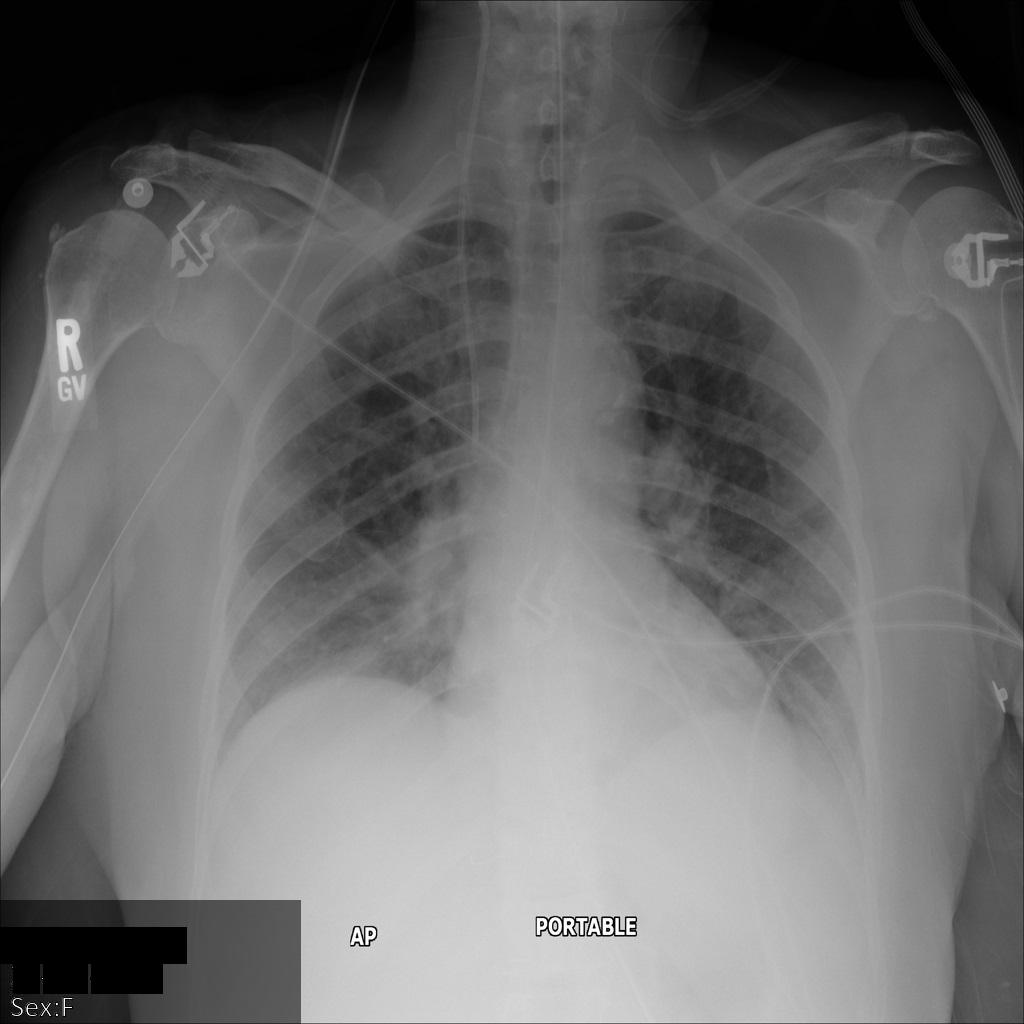

Chacune des sections suivantes fournit des exemples d'anonymisation de données DICOM à l'aide de différentes méthodes. Une sortie de l'image anonymisée est fournie avec chaque échantillon. Chaque exemple utilise l'image d'origine suivante comme entrée :

Vous pouvez comparer l'image de sortie de chaque opération d'anonymisation à cette image d'origine pour voir les effets de l'opération.

Une fois l'image envoyée à l'API Cloud Healthcare, elle apparaît comme suit. À l'exception des balises fournies dans la liste de suppression, seul PatientBirthDate est supprimé dans l'image, car il s'agit de la seule balise de la liste de suppressions qui correspond aux métadonnées visibles dans l'image.

Bien que le PatientBirthDate dans l'angle supérieur de l'image ait été masqué conformément à la configuration de la liste removelist, les données de santé protégées incrustées en bas de l'image sont conservées. Pour supprimer également le texte incrusté, consultez la section Masquer le texte incrusté dans les images.